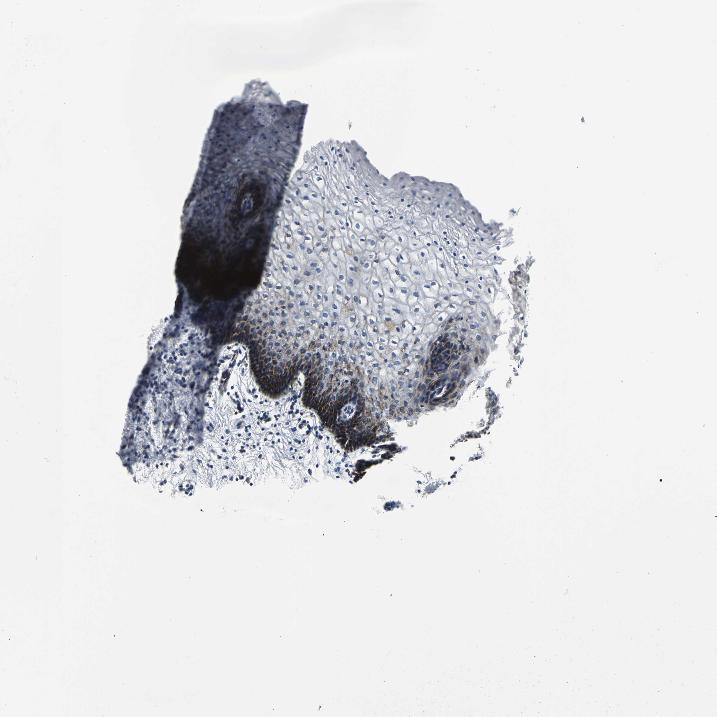

VAGINA - Antibody stainingi

Antibody staining in the annotated cell types in the current human tissue is reported as not detected, low, medium, or high, based on conventional immunohistochemistry profiling in selected tissues. This score is based on the combination of the staining intensity and fraction of stained cells.

Each image is clickable and will lead to virtual microscopy that enables deeper exploration of all samples and also displays staining intensity scores, fraction scores and subcellular localization as well as patient and tissue information for each sample.

Antibody HPA005543

Squamous epithelial cells Medium